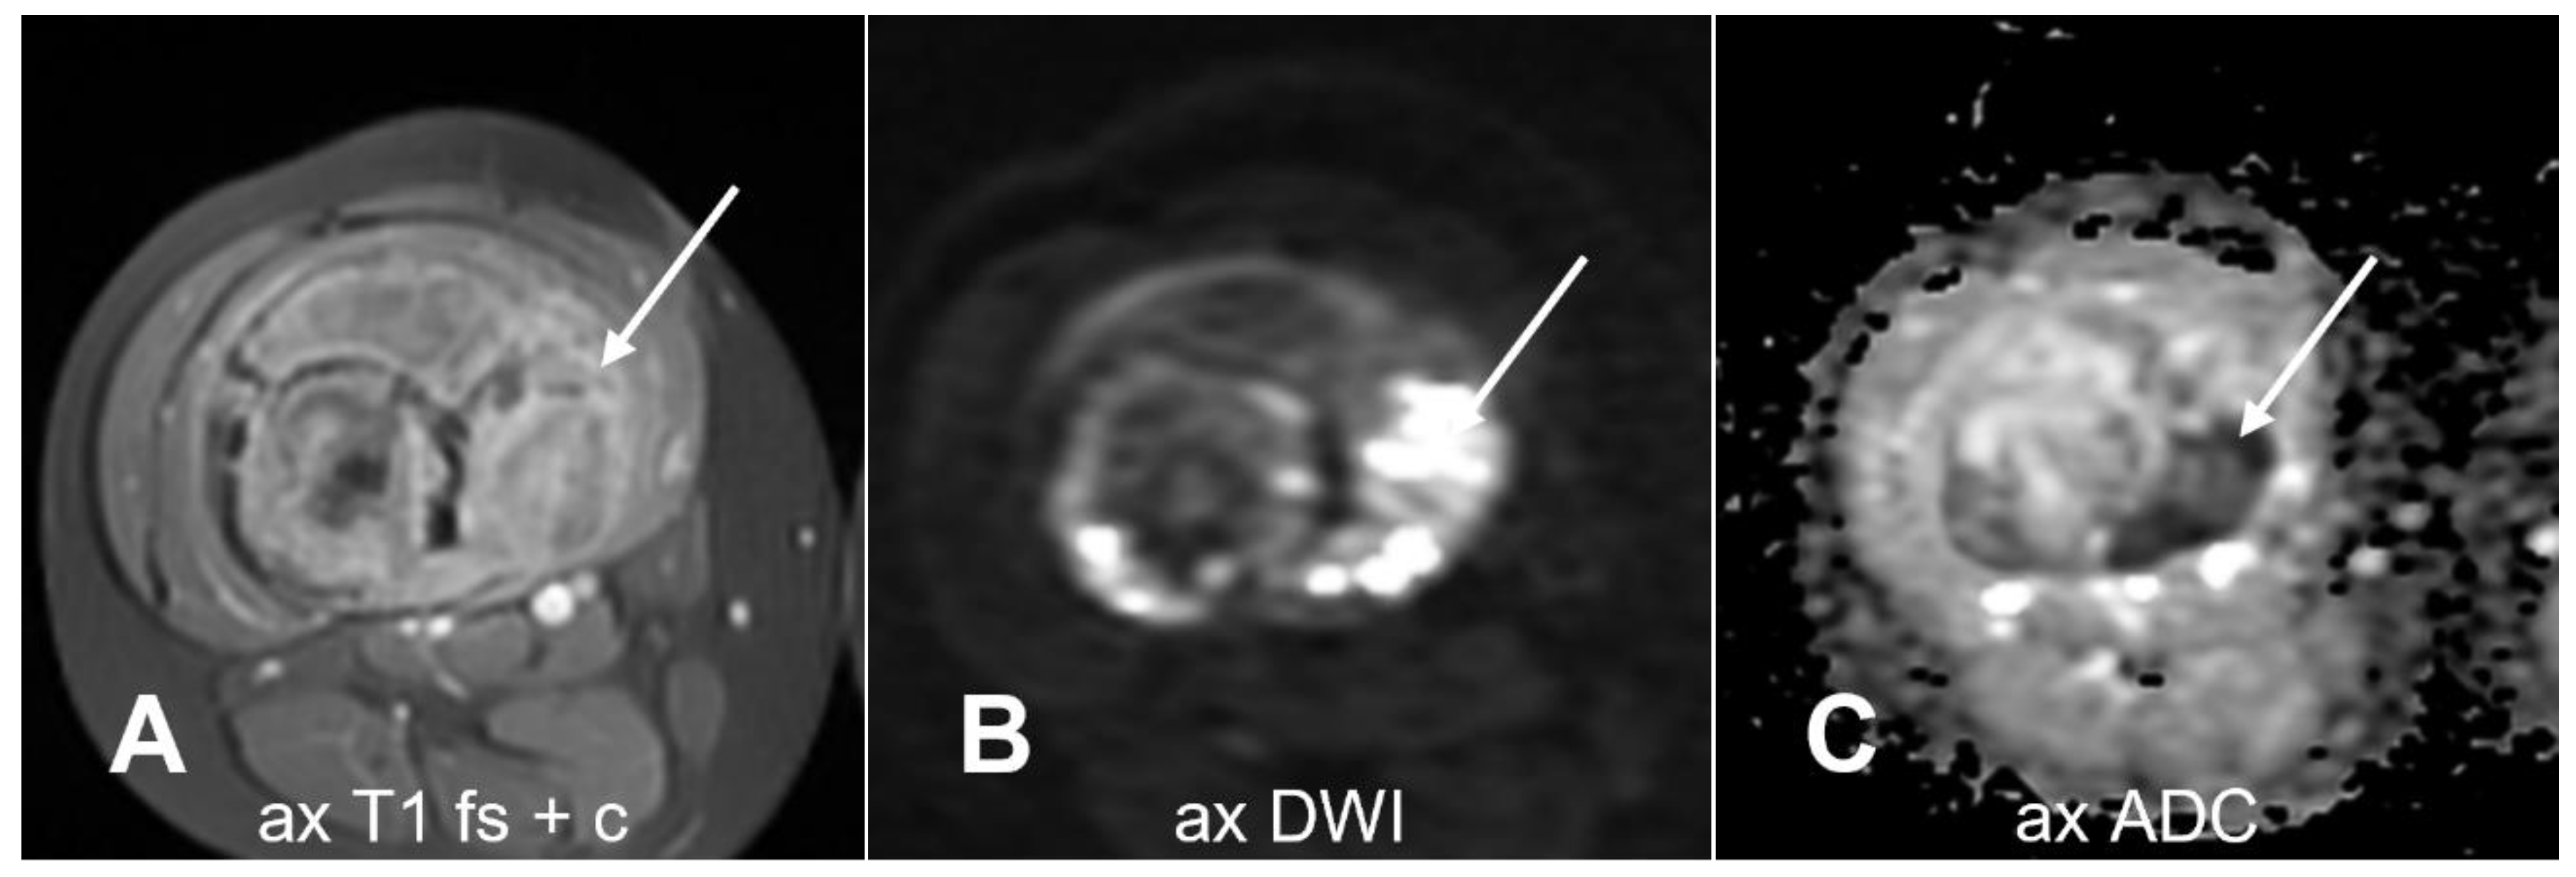

- Bammer, R. Basic Principles of Diffusion-Weighted Imaging. Eur. J. Radiol. 2003, 45, 169–184. [Google Scholar] [CrossRef]

- Guadilla, I.; Calle, D.; López-Larrubia, P. Diffusion-Weighted Magnetic Resonance Imaging. In Preclinical MRI. Methods in Molecular Biology; García Martín, M., López Larrubia, P., Eds.; Humana Press: New York, NY, USA, 2018; Volume 1718, pp. 89–101. [Google Scholar]

- Bajpai, J.; Gamnagatti, S.; Kumar, R.; Sreenivas, V.; Sharma, M.C.; Khan, S.A.; Rastogi, S.; Malhotra, A.; Safaya, R.; Bakhshi, S. Role of MRI in Osteosarcoma for Evaluation and Prediction of Chemotherapy Response: Correlation with Histological Necrosis. Pediatr. Radiol. 2011, 41, 441–450. [Google Scholar] [CrossRef] [PubMed]

- Hayashida, Y.; Yakushiji, T.; Awai, K.; Katahira, K.; Nakayama, Y.; Shimomura, O.; Kitajima, M.; Hirai, T.; Yamashita, Y.; Mizuta, H. Monitoring Therapeutic Responses of Primary Bone Tumors by Diffusion-Weighted Image: Initial Results. Eur. Radiol. 2006, 16, 2637–2643. [Google Scholar] [CrossRef] [PubMed]

- Hao, Y.; An, R.; Xue, Y.; Li, F.; Wang, H.; Zheng, J.; Fan, L.; Liu, J.; Fan, H.; Yin, H. Prognostic Value of Tumoral and Peritumoral Magnetic Resonance Parameters in Osteosarcoma Patients for Monitoring Chemotherapy Response. Eur. Radiol. 2021, 31, 3518–3529. [Google Scholar] [CrossRef] [PubMed]

- Zampa, V.; Aringhieri, G.; Tintori, R.; Rossi, P.; Andreani, L.; Franchi, A. The Added Value of the Visual Analysis of DWI in Post-Surgery Follow-up of Soft Tissue Sarcoma of the Extremities: Do We Really Need ADC? Radiol. Med. 2023, 128, 467–479. [Google Scholar] [CrossRef] [PubMed]

- Teo, K.Y.; Daescu, O.; Cederberg, K.; Sengupta, A.; Leavey, P.J. Correlation of Histopathology and Multi-Modal Magnetic Resonance Imaging in Childhood Osteosarcoma: Predicting Tumor Response to Chemotherapy. PLoS ONE 2022, 17, e0259564. [Google Scholar] [CrossRef]